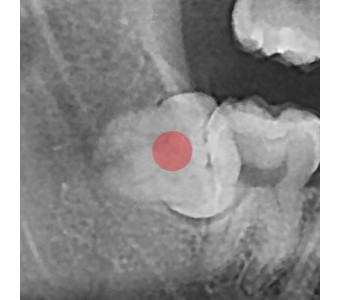

정확성 높은 치료의 시작 디지털 정밀진단 시스템

3D 디지털 데이터 기반으로 정확성 높고 정교한 치료가 가능합니다.

결과로 증명합니다.

국제모아치과의

실제 임상 증례